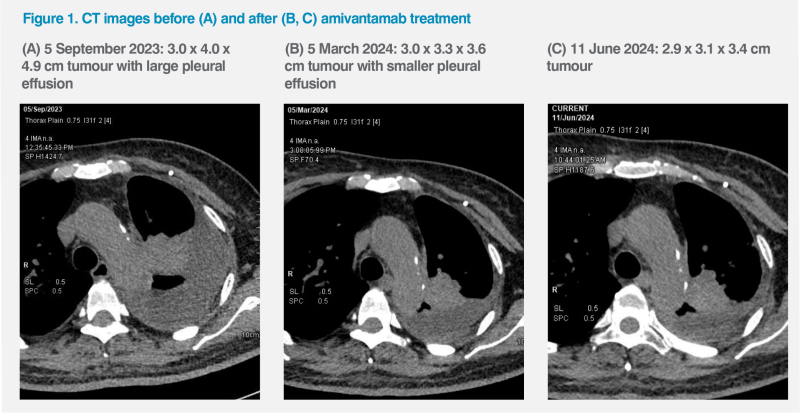

During this period, bevacizumab was stopped and her disease progressed. PET-CT thorax in September 2023 showed that the paramediastinal mass in the LUL had enlarged to 3.0 x 4.0 x 4.9 cm, while the number of lung nodules (>20) and left pleural effusion had increased. (Figure 1A) Her CEA level increased to 37.4 μg/L. The patient was mostly bedbound and required feeding assistance. Her body weight was 59 kg, and her ECOG PS deteriorated to 3. (Table)

The patient achieved a PR to amivantamab. Her CEA level decreased from 72.7 μg/L in October 2023 to 49 μg/L in December 2023 and further dropped to 22 μg/L in July 2024. CT Thorax showed the primary LUL mass reduced to 3.0 x 3.3 x 3.6 cm in March 2024 and 2.9 x 3.1 x 3.4 cm in June 2024, with decrease in number of lung nodules and reduction of left pleural effusion. (Figure 1B and 1C)